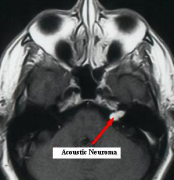

问:听神经瘤的主要临床表现有哪些?听神经瘤术后有后遗症吗? 答:听神经瘤是从内耳道到小脑桥角部发展的良性肿瘤,但很少是恶性的。大多数肿瘤起源于前庭雪旺氏细胞,因此恰...

问:听神经瘤早期可以检查出来吗? 答:听神经瘤诊断很多时候会出现不满意的情况,诊断仍然是听神经瘤疾病链中较薄弱的环节:早期和晚期症状 - 诊断 - 治疗决策 - 治疗 - 康复。这...

问:听神经瘤治疗会有什么后遗症? 答: 听神经瘤 是一种良性肿瘤,从负责听觉和平衡神经发生。良性肿瘤不会扩散到身体的其他部位,但它们仍然可以长到足以压迫周围组织,需要...